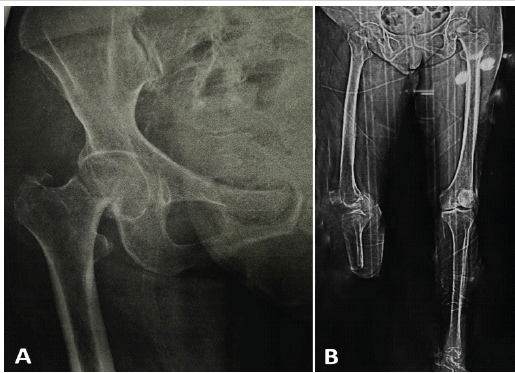

The patient, a 55-year-old woman, was brought to the hospital with a complaint of pain in the right hip after a fall at home. She had undergone a BKA of the right lower limb 9 months earlier due to complications of a diabetic foot. After the amputation, she began walking with a below-knee prosthesis and a walker inside her domicile. Based on the observations of her family members, she had not fully adapted to the prosthesis, which eventually led to a fall while walking on a patch of unpaved ground in the courtyard of her domicile. Radiographs revealed a right-sided femoral neck fracture (Fig. 1a). We also obtained a scanogram of the lower limbs (Fig. 1b).

Figure 1: (a) Pre-operative radiograph of the right hip showing a fracture in the neck of the femur, (b) full-length scanogram of both the lower limbs.